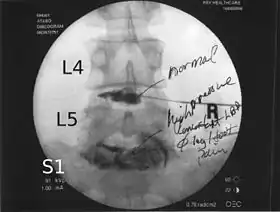

![]() Lumbar provocative discography showing a degenerated disc, L5-S1 with normal disc L4-L5 | |

Spinal MRI is the imaging of choice to investigate the spine and intervertebral discs.[1] Meanwhile, lumbar discography is used to demonstrate degeneration and herniation of lumbar intervertebral discs by injecting a dye into the nucleus pulposus of the discs. The procedure is also used to reproduce pain back pain for those who have such symptoms. Lumbar discography is also used to access the response of a subject to anaesthetic injection. Other uses include suspected discogenic pain without radicular sign (pain travelling to lower limbs along a dermatome) and confirmation of normal intervertebral discs above and below a site before spinal fusion.[1] However, evidence supporting the usefulness of lumbar discography in recognizing intervertebral disc problems is limited.[1] There is no role for cervical or thoracic discography in diagnosing disc pathologies at the cervical or thoracic regions.[1][2]

Non-ionic contrast media such as iopamidol and iohexol are used.[1] Needles are inserted through the back into the disc near the suspect area, guided by fluoroscopic imaging. Fluid is then injected to pressurize the disc, and any pain responses are recorded.

A contrast agent is introduced, and after the procedure, a CT scan identifies leakage from the discs to identify any spinal disc herniation.